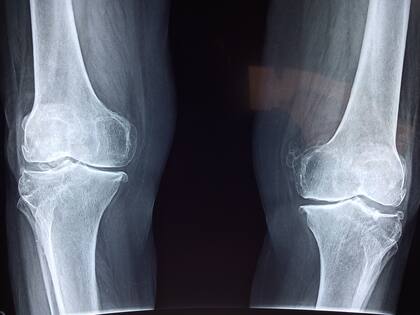

Además, no solo los dedos pueden generar estos sonidos característicos. Las rodillas, por ejemplo, también son susceptibles a producir un crujido similar, a menudo sin implicar riesgos significativos. Este sonido puede resultar del roce entre estructuras óseas o tendinosas, y como en el caso de los nudillos, no hay una forma estándar de prevenirlo.